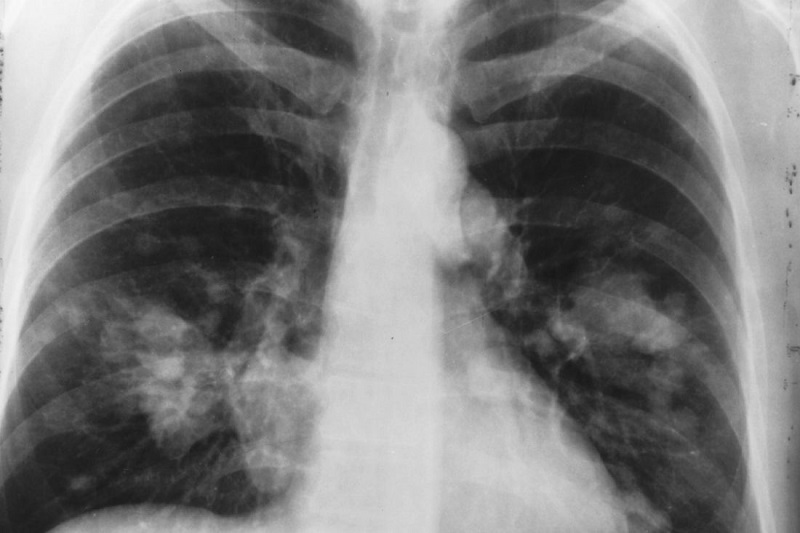

به گزارش ایران اکونومیست از پایگاه خبری ساینس دیلی، سرطان ریه سلول غیر کوچک یا NSCLC مرگبارترین نوع سرطان ریه است؛ چراکه تا مراحل پیشرفته تشخیص داده نمی شود و امکان جراحی و درمان را در اختیار پزشک قرار نمی دهد.

بر اساس آمار مرکز کنترل و پیشگیری از بیماری ها، سرطان ریه علت اصلی مرگ و میر ناشی از سرطان و دومین سرطان شایع است. از هر چهار مرگ ناشی از سرطان، یک مورد به دلیل سرطان ریه است. مطالعات نشان می دهد تشخیص و درمان سریع بیماری موثرترین روش در افزایش طول عمر بیمار است.